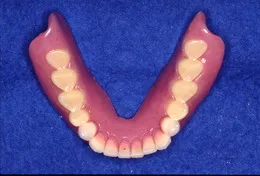

総入れ歯で肝心なのは顎(顎堤)にぴったりあっていることと咬み合わせがしっかりしていることでしょう。入れ歯で困っている方には原因があります。丁寧に診査し解決策を探りましょう。

当院では治療用の入れ歯を使って顎にぴったりとあった形を導きます。ぴったりあった入れ歯を入れると口元も自然感を取り戻せます。「急がばまわれ」、少し時間をかけて使いやすい入れ歯を手に入れましょう。

また、咬み合わせは癖が出やすいものです。調和のとれた咬み合わせにするには『咬合採得』の技術が必要です。当院では治療ステップを正確に行うため安定した咬み合わせの総入れ歯を装着できます。

(顎の形にしっかりフィットして咬み合わせが安定した入れ歯ができあがりました)